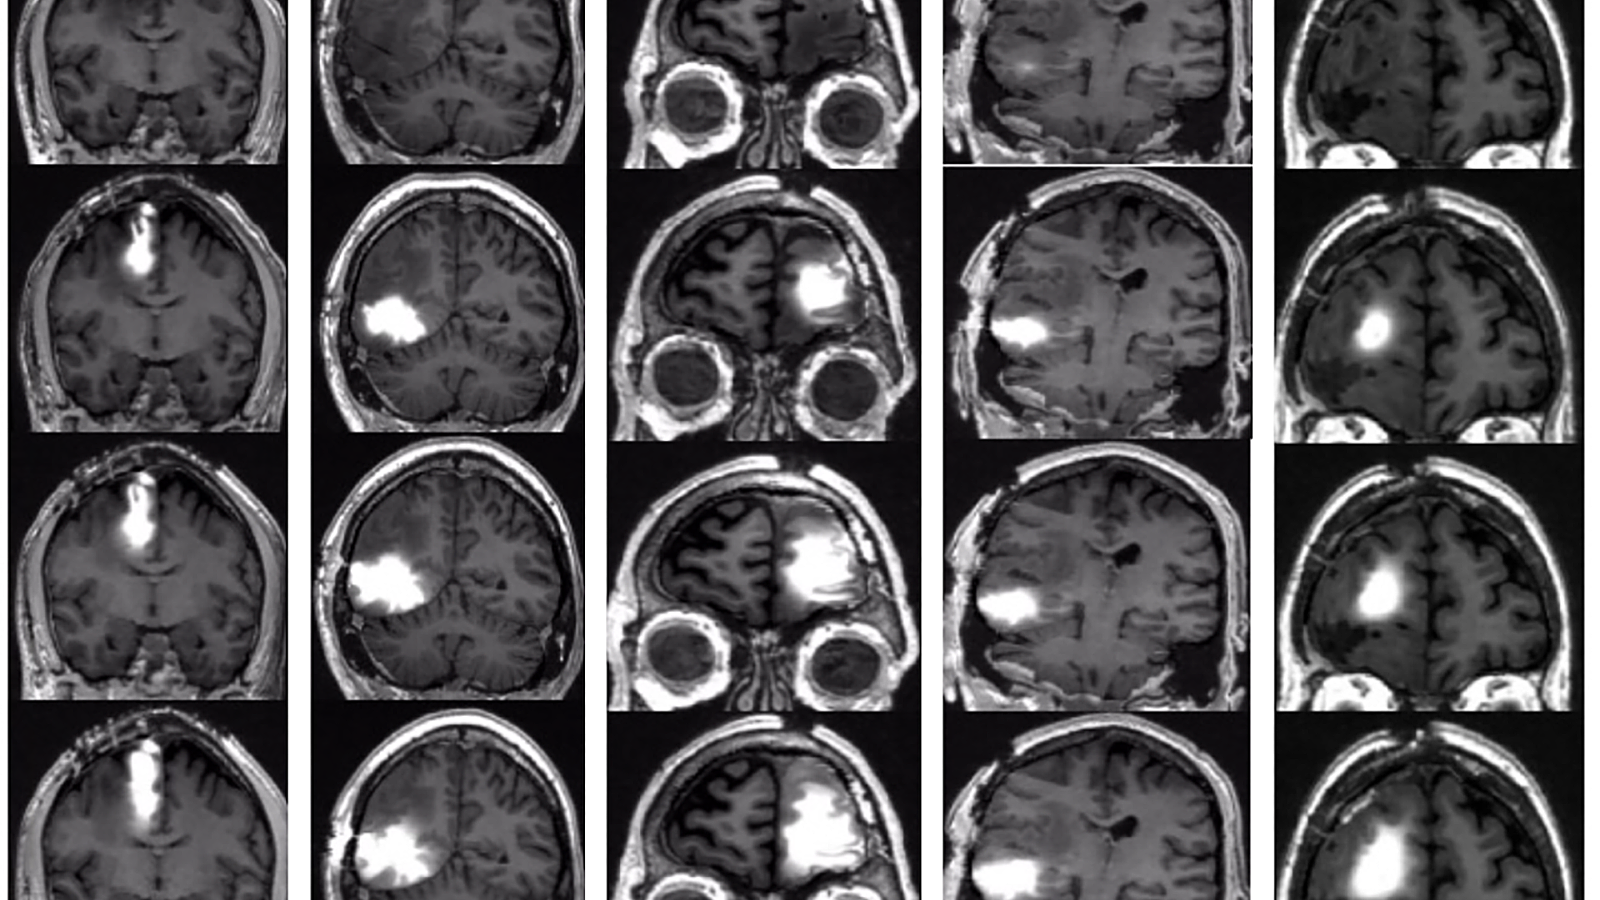

A new brain cancer vaccine can extend some glioblastoma patients’ lives by months or even years, according to its maker — but the design of the company’s trial has some questioning the claims.

The challenge: The standard treatment for glioblastoma — the most aggressive form of brain cancer — starts with surgery to remove as much of the tumor as possible. After that, patients typically undergo chemotherapy and radiation therapy to kill lingering cancer cells.

But even with treatment, the prognosis for glioblastoma isn’t great — the cancer almost always comes back, and patients live an average of just 12 to 18 months after diagnosis.